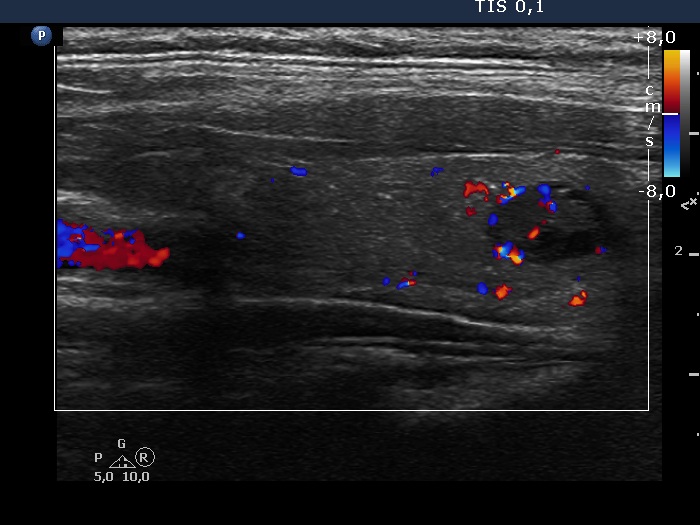

Ultrasonography. The thyroid was echonormal. There were two nodules in the left lobe. The upper lesion was a dominantly isoechoic nodule which had microcalcifications while the lower one was a hypoechoic nodule. There were numerous microcalcification relatively far from the primary tumor focus. The upper nodule was avascular while the lower one presented both intranodular and perinodular blood flow.

A conglomerate of lymph nodes was found 2 cm above the left lobe. The nodes did not have hilum but contained microcalcifications and presented irregular vascular pattern. (This was not noticed on the previous ultrasound examination.)